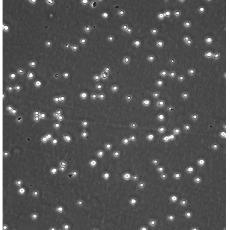

中文名稱(chēng) 人急性淋巴細(xì)胞白血病細(xì)胞

組織來(lái)源 急性T淋巴細(xì)胞白血病;女性

生長(zhǎng)特性 suspension

形態(tài)特征 lymphoblast

細(xì)胞描述 CEM/C1是人T細(xì)胞白血病細(xì)胞株CCRF-CEM(見(jiàn)ATCC CCL-119)具有喜樹(shù)堿抗性的衍生株。1991年細(xì)胞株選擇并亞克隆了對(duì)CPT的抗性。細(xì)胞表現(xiàn)出對(duì)CPT類(lèi)似物水溶性的托泊替康和非水溶性的9-氨基-CPT及10,11-亞甲二氧基-CPT具有交叉抗性。CEM/C1細(xì)胞對(duì)CPT的敏感性較母系CEM細(xì)胞低31倍。CEM/C1細(xì)胞表現(xiàn)非典型的多藥抗性和轉(zhuǎn)換拓補(bǔ)異構(gòu)酶I催化活性。對(duì)CPT的抗性維持6個(gè)月以上。